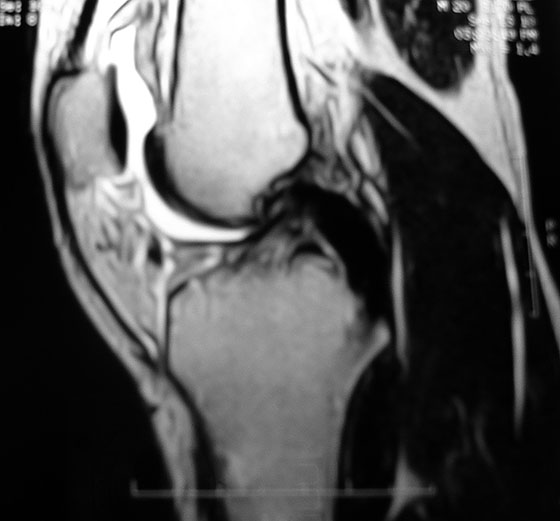

Control de RMN de paciente con 2 años de postoperatorio (Fig. 15).